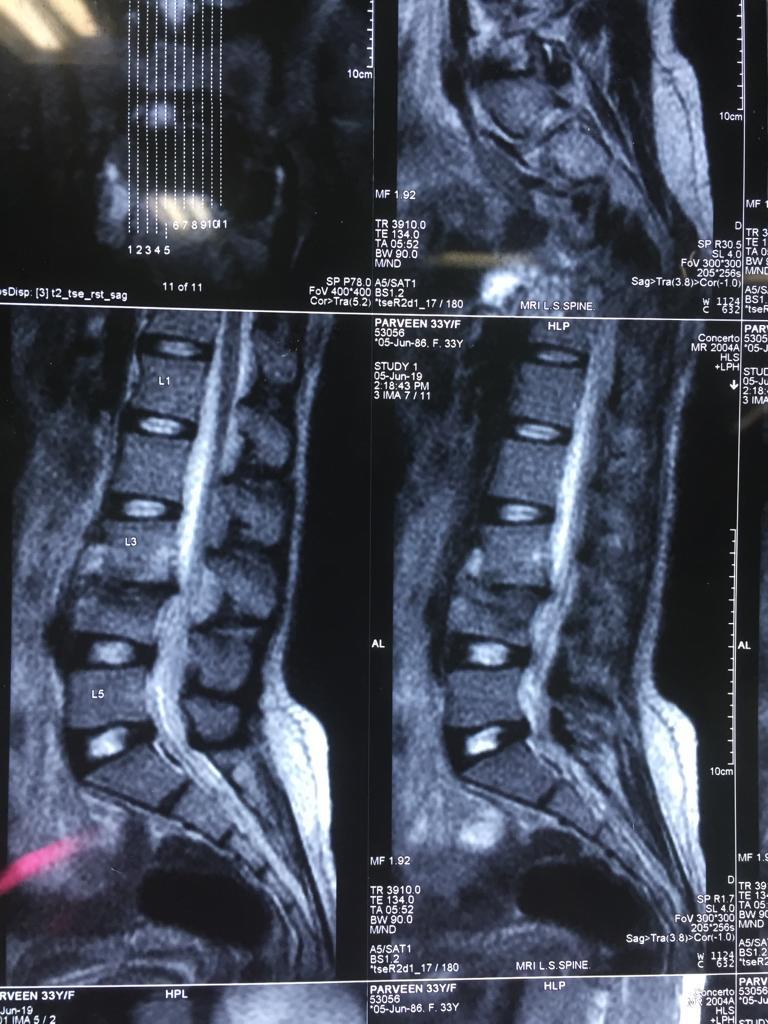

Cases